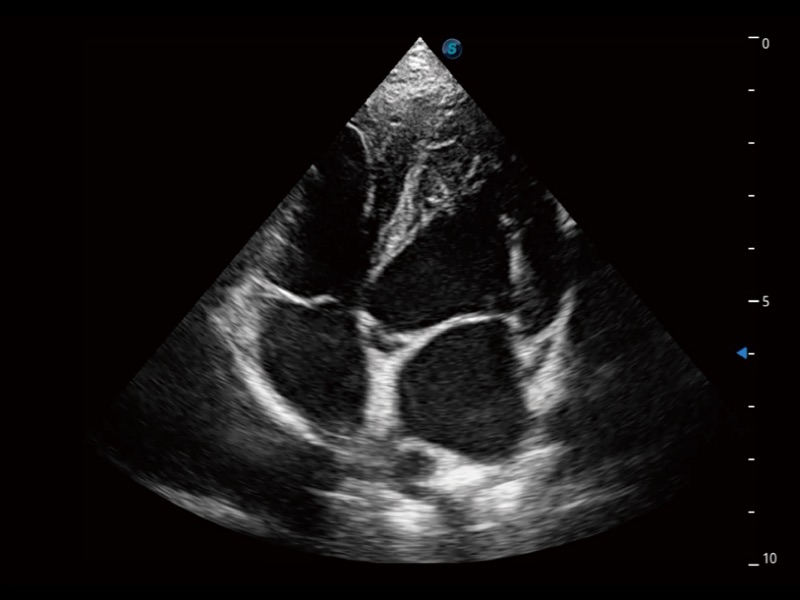

ProPet 70专为动物医生设计,对不同的动物体型和生理结构作出了针对性的优化。通过动物影像专用软件,可满足个性化的应用需求,帮助动物医生获得更精确的诊断数据。

为精细结构及组织边缘提供高清晰度的图像和更大的成像视野。帮助减轻医生的用眼疲劳,快速精准获得测量的数据。

ProPet 70 全新的动物超声智能软件和丰富的探头群,为动物医生提供了高清晰度和精细分辨率的图像,无论在宠物、马科、畜牧还是实验室动物等应用中都可以轻松应对,为您的日常工作带来满意的体验。